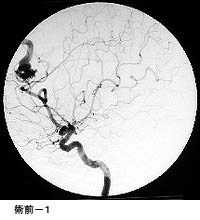

破裂脳動脈瘤に対するGDC(コイル)塞栓術

術後 コイルにより動脈瘤が写らなくなりました。